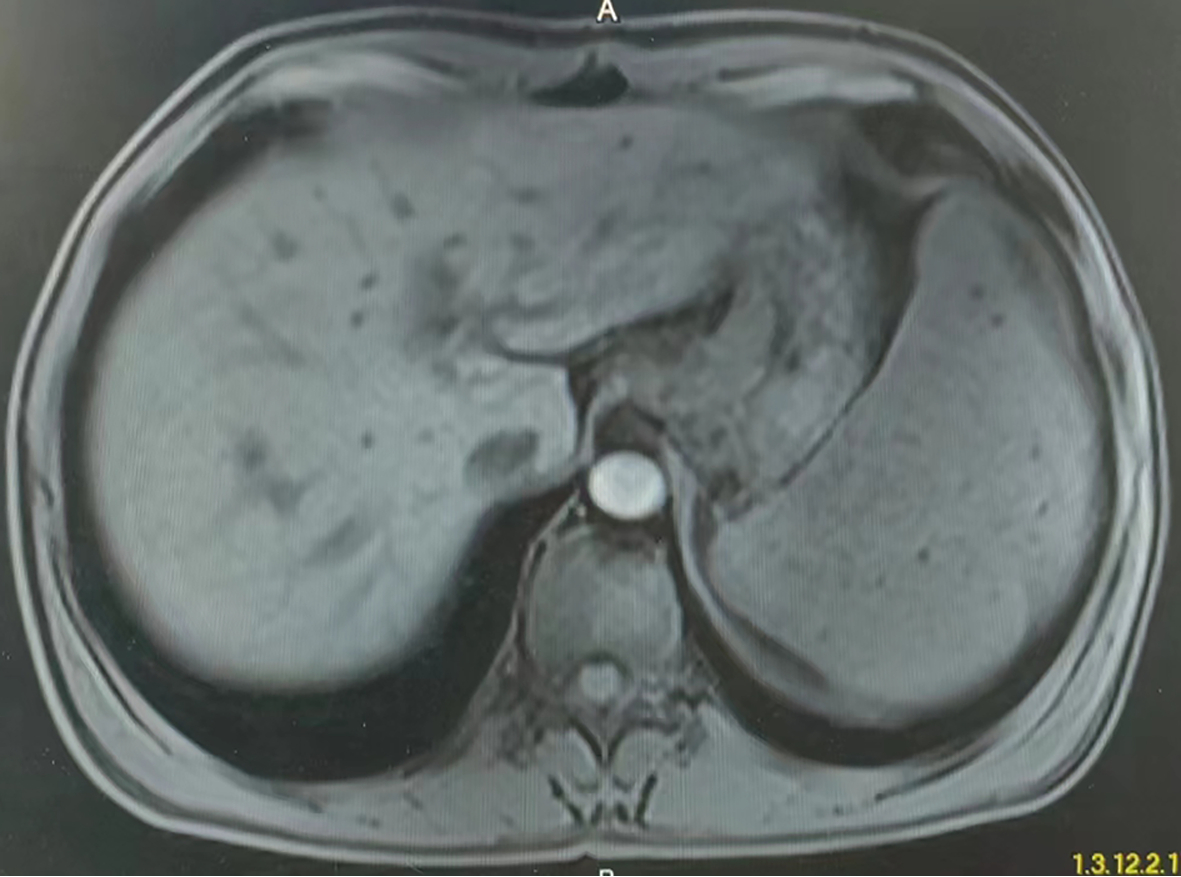

Clinical features of myeloproliferative neoplasms with portal hypertension as the main manifestation

Lijuan FENG, Yan WANG, Min WANG, Guanhua ZHANG, Fuliang HE, Xinyan ZHAO, Yu WANG

2023, 39(2): 365-369. DOI: 10.3969/j.issn.1001-5256.2023.02.017

Abstract(1329) HTML (502) PDF (2315KB)(119)

Abstract:

Objective  To investigate the clinical features, liver histological features, and diagnostic and treatment methods for patients with myeloproliferative neoplasms (MPN) with portal hypertension as the main manifestation.  Methods  A retrospective analysis was performed for related data of the patients who attended the hospital due to portal hypertension and were finally diagnosed with MPN in Liver Research Center, Beijing Friendship Hospital, from January 2019 to February 2022, including clinical manifestation, liver pathological features, treatment, and follow-up results.  Results  Nine patients were included in this study, and all the patients had splenomegaly and esophageal and gastric varices, while portal vein thrombosis was observed in eight patients. All patients had normal or slightly abnormal liver function and routine blood test results. Six patients underwent liver biopsy, without the formation of fibrous septum and pseudolobule, and hepatic extramedullary hematopoiesis was observed in two patients. All nine patients underwent bone marrow biopsy and genetic testing, among whom six had essential thrombocythemia and three had primary myelofibrosis, and genetic testing revealed JAK-2V617F gene mutation in seven patients and CALR gene mutation in two patients.  Conclusion  MPN is one of the rare causes of portal hypertension and has the clinical manifestations of esophageal and gastric varices, splenomegaly, and even megalosplenia, without the manifestations of hypersplenism such as leukopenia and thrombocytopenia. Detection of the JAK-2V617F and CALR genes can improve the diagnostic rate of MPN.